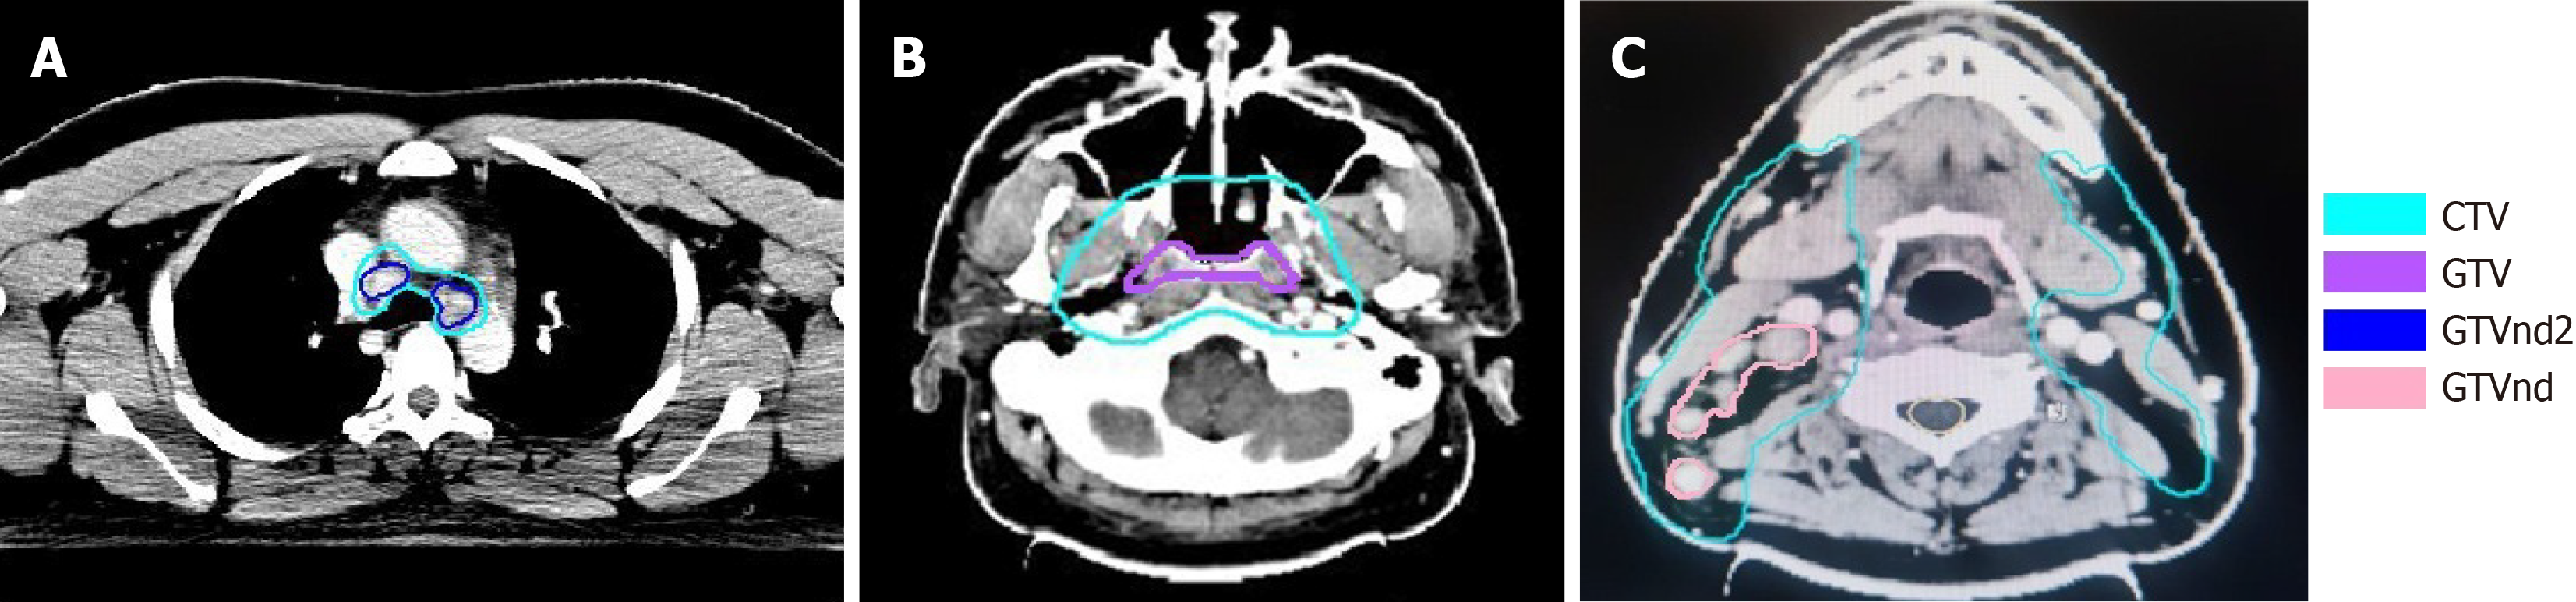

Figure 6 Delineation of the target area for local intensity modulated radiotherapy plan.

A: Lung target area: GTVnd2 = 2 Gy × 33f, CTV = 1.82 Gy × 33f; B: Nasopharynx target area: GTV = 2.12 Gy × 33f, CTV = 1.82 Gy × 33f; C: Neck Lymph Nodes: GTVnd1 = 2.12 Gy × 33f, CTV = 1.82 Gy × 33f. CTV: Clinical target volume.